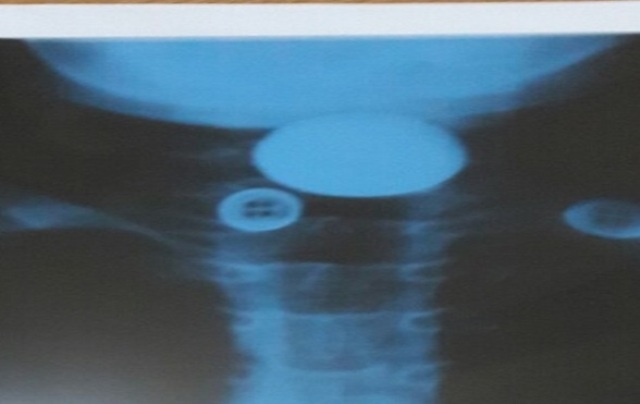

Tại đây, các bác sĩ chỉ định cho bệnh nhi chụp X-quang, hình ảnh cản quang cho thấy dị vật là một hình tròn như đồng xu ngang đốt cổ C5, C6, vị trí ngang giữa cổ. Ngay lập tức bệnh nhi được đưa vào phòng gây mê và tiến hành nội soi gắp dị vật.

| Hình ảnh chụp X-quang cho thấy dị vật mắc kẹt ở vị trí đốt sống cổ C5, C6. Ảnh: BSCC. |

Bác sĩ CKII Nguyễn Anh Dũng, phụ trách khoa Tai mũi họng, cho biết sau khi nội soi phát hiện dị vật là một đồng xu nằm ngang, cách miệng 4-5 cm.